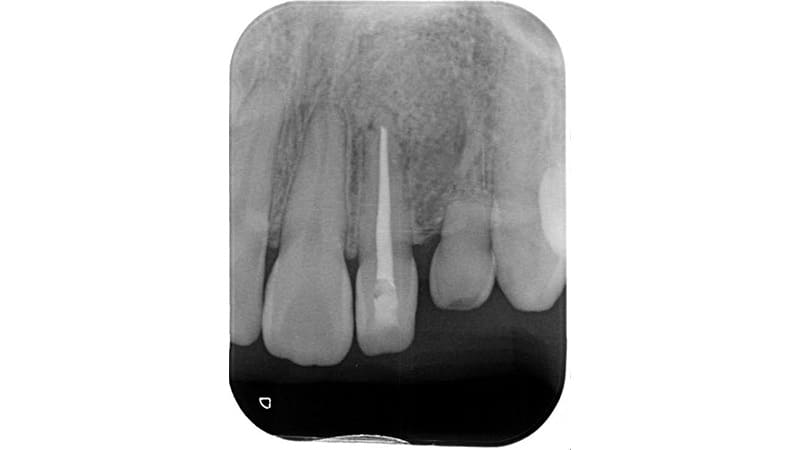

症例③:数年前に治療した歯の横が腫れてきた

| 治療科目 | 歯根端切除術 |

|---|---|

| 主訴 | 数年前に治療した歯の横が腫れてきた |

| 治療期間 | 3ヶ月 |

| 治療費 | 約10,000円(保険適応) |

| 治療内容 | 歯茎を横から切開し原因である病巣を摘出し、縫合します。 |

| 治療のリスク | 歯根が短くなるため破折のリスクがあります。またまれに再発することもあります。 |